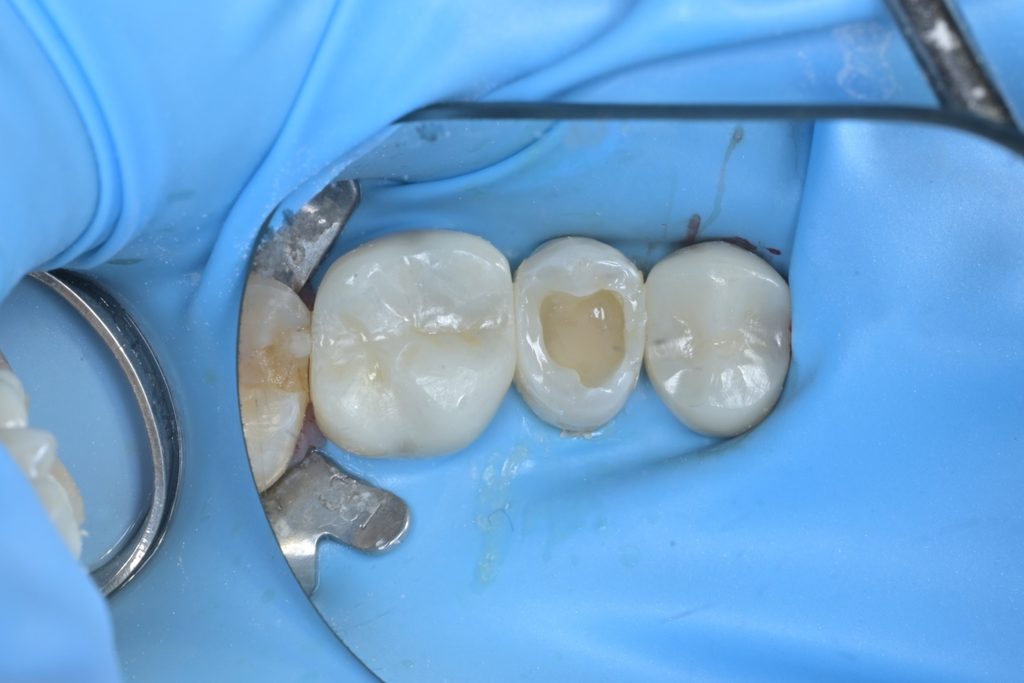

치료 후 최종 마무리 및 결과

레진빌드업 완료 후, 교합지를 이용하여 반대편 치아와의 교합 접촉을 세밀하게 조정하고, 다이아몬드 버와 폴리싱 시스템을 사용하여 최종 연마를 진행했습니다.

[사진14: 협측면에서 본 최종 치